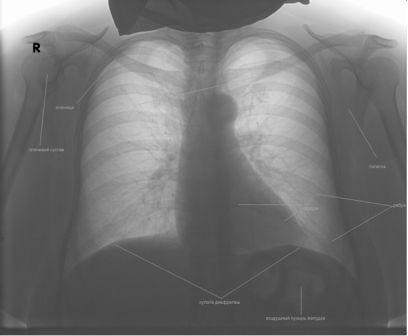

Следует понимать, что рентген-картина заболеваний зависит от различного сочетания и комбинации между собой вышеописанных симптомов. На особенности ее описания врачом-рентгенологом не влияет также разновидность снимка (негатив или позитив). Ниже приведен снимок легких в позитиве, аналогичный первому.

Несмотря на разный вид обоих рисунков в статье, описание их легких рентгенологом не отличается, так как это один снимок в негативе и позитиве.